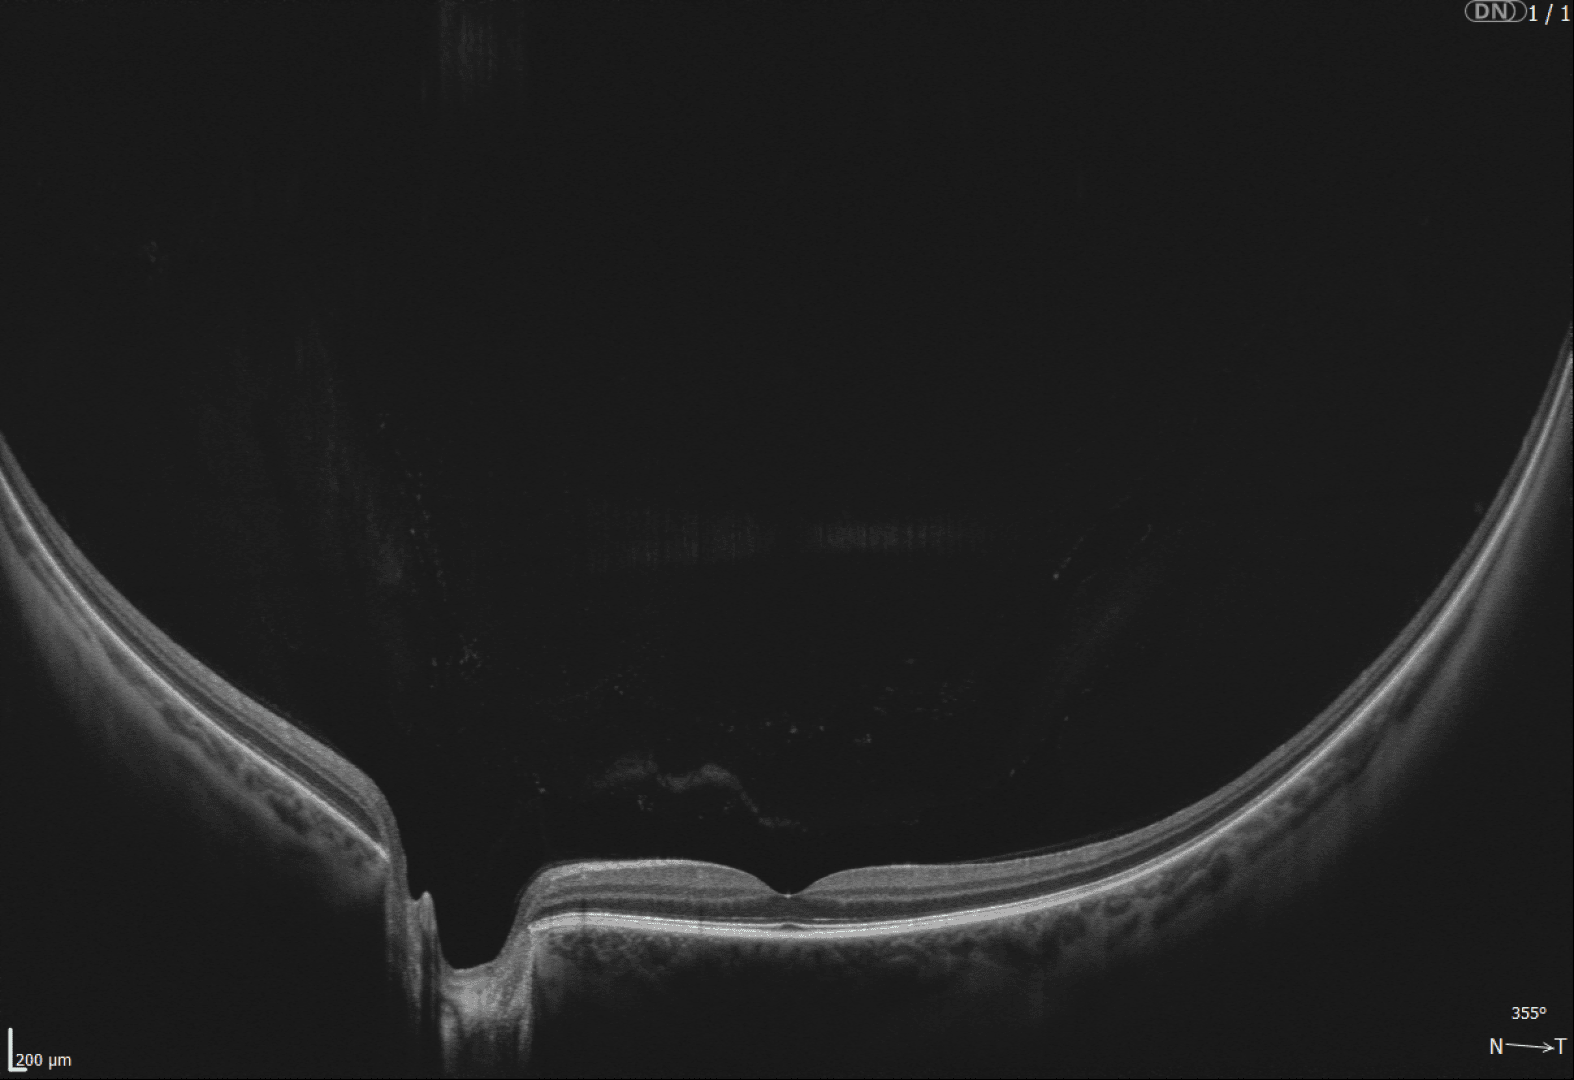

REVO OCT's - KI-basiertes OCT-Screening so einfach wie nie

Die Optopol REVO OCT-Serie überzeugt durch einen beeindruckend breiten Funktionsumfang und ein hervorragendes Preis-Leistungs-Verhältnis. Von Netzhautscreening bis Myopie-Management - alles ist möglich. Testen Sie Ihr Wunschgerät unverbindlich in einer Demostellung in Ihrem Geschäft.

Entdecken Sie die REVO OCT-Familie von Optopol, die für jede Anwendung das passende Modell bietet. Die ideale Wahl für Preisbewusste ist das REVO ECO. Das REVO FC bietet eine integrierte Funduskamera. Oder das ultra-schnelle SD-OCT für höchste Ansprüche: das REVO NX 130 und das REVO FC 130 mit integrierter Funduskamera.

Alle Modelle überzeugen durch ihre Vollausstattung: Netzhaut-Screening, Glaukom-Analyse, Vorderabschnitt-Scans, Gonioskopie und Pachymetrie - alles vollautomatisch und gestützt durch eine normative Datenbank zur unabhängigen Befundbewertung. Optional erweitern Funktionen wie Biometrie, Hornhauttopographie und OCT-Angiographie die Einsatzmöglichkeiten.